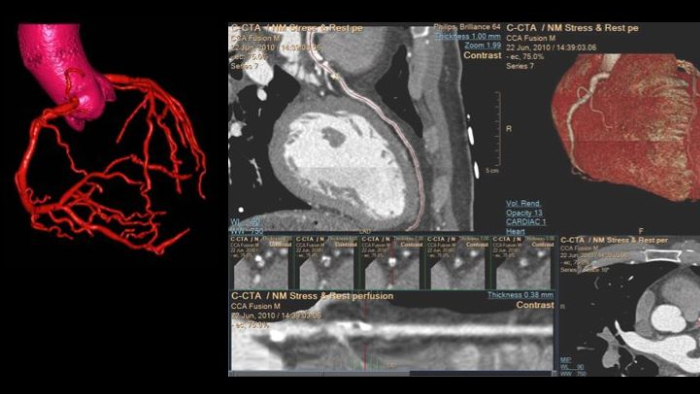

Spectral CT 7500

Unlock the full potential of a Philips CT as a non-invasive cardiac diagnostic tool.

Advanced Visualization Workspace

Review, analyze and quantify clinical information from different modalities and for various clinical indications with AI-enabled 3D models, maps and other quantitative tools.